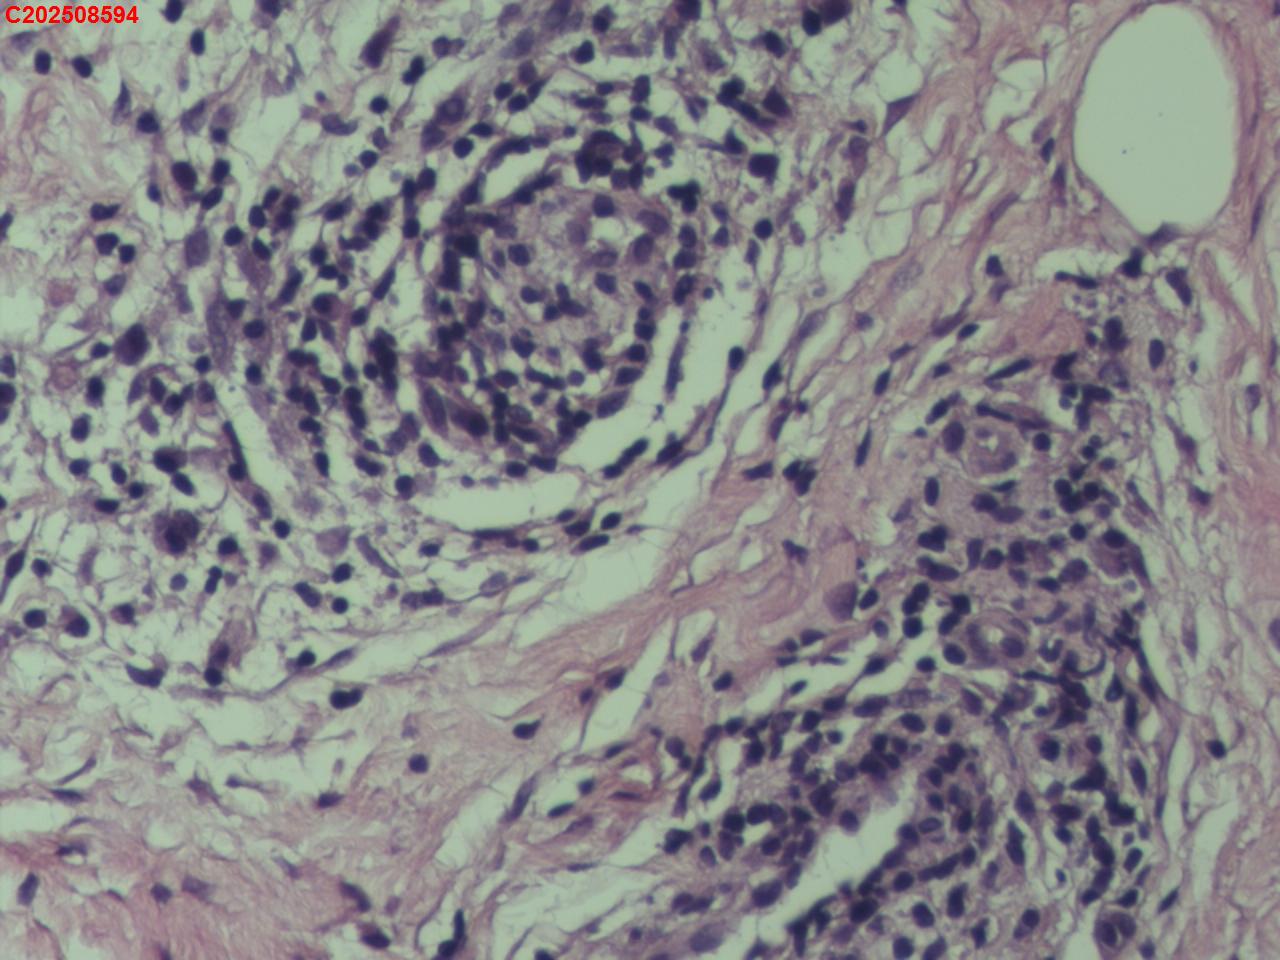

腰椎椎旁穿刺组织

性别年龄50岁临床诊断腰椎椎旁脓肿性质待查?

标本名称腰椎椎旁穿刺组织

大体所见腰椎椎旁穿刺组织2条

患者缘于入院前3个月无明显诱因出现腰腹痛,起初为隐痛,间断对症治疗,症状进行性加重,故入院前20天于某市第五医院就诊,查腰椎X片提示腰椎骨质增生,给予布洛芬、双氯芬酸钠等对症治疗,症状仍进行性加重,疼痛级别为5级,休息不能缓解,故入院前5天于某市第一人民医院就诊,查腰椎CT提示腰椎间盘膨出,腰椎退行性变,双侧腰大肌及背侧肌群增粗模糊致左侧输尿管下段粘连,尚短输尿管及肾盂扩张积水,腰背部皮下积液,嘱其回当地医院治疗,故入院前2天于某县中医院查彩超提示左侧腹腔内低回声包块,双肾积水、双侧输尿管上段扩张,右肾多发结石,遂于某市第二医院住院治疗,住院期间查CT提示双侧腰大肌及髂腰肌增厚、肿胀,左肾及输尿管腹段积水改变,腹膜后及左侧腹股沟区稍大淋巴结,左肺上叶及右肺中叶条索,胆囊多发结石子宫切除术后改变;血糖、肝肾功能、血脂基本正常,考虑腹腔结核可能。

描述诊断,未见结核病灶